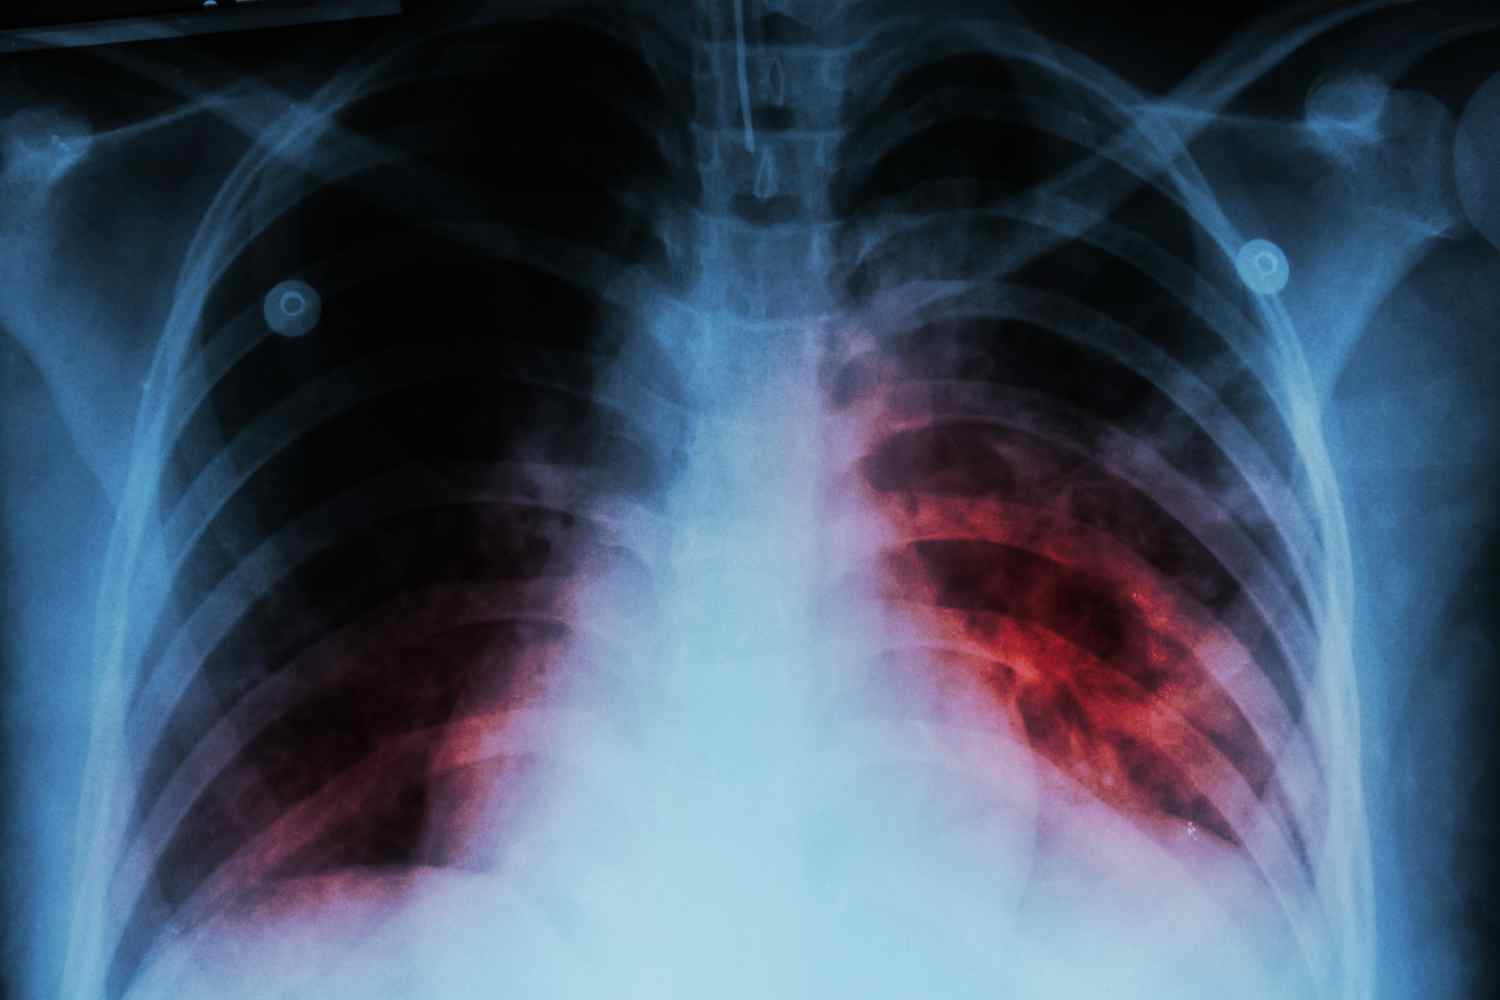

La tuberculosis ha vuelto a León. Esta enfermedad infecciosa, causada por una bacteria que afecta a los pulmones, ha sido la causa de la muerte de un inmigrante que llegó a León a través del programa de protección internacional del Ministerio de Inclusión,Seguridad Social y Migraciones.

Según la información publicada por el Diario de León, el fallecimiento tuvo lugar hace un mes cuando un veinteañero presentó síntomas de esta enfermedad y fuese derivado a atención primaria para después ser trasladado al Hospital de la capital. Fue entonces cuando la enfermedad acabó con su vida, debido a una explosión pulmonar.

Los síntomas que saltaron las alertas fueron la tos crónica y el dolor en el torax, una vez en el centro de salud de Armunia, se efectuaron sus pruebas y los posibles contagios. La enfermedad se confirmó, y no solo en él, pues otros 20 inmigrantes resultaron positivos, aunque la mayoría tenian la enfermedad sin desarrollar, tal y como asegurá el medio leonés.

A pesar de que la tuberculosis es una de las enfermedades más letales del planeta, superada como infección por el COVID-19, este mal puede curarse, gracias a los fármacos, en unos cuatro o seis meses.